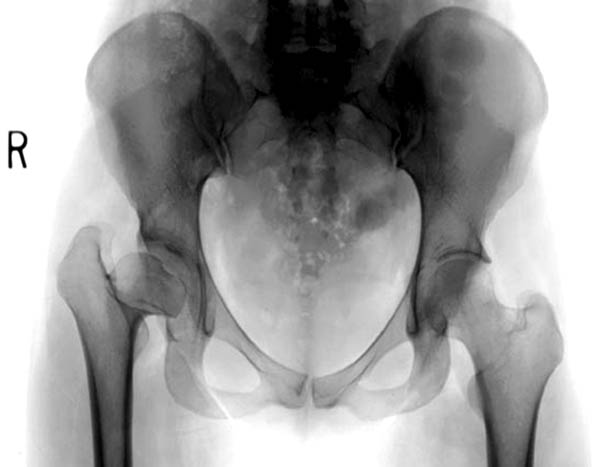

Здесь комбинированная патология тазобедреннего сустава, связанная с высокостоящим вертелом и отсутствием (ротирована?) шейкой. А на стороне вертлужной впадины диспластический сустав. Обычно высоко расположенный вертел приводит к уменьшению силы мышц абдукторов, но отстутствие шейки привело к вертикальному расположению сил в суставе. Боли появляются из-за вертикального давления, а неровные контуры головки приводят к ограничению движений в суставе. Такое состояние быстро изнашивает сустав, и больные в молодом возрасте заканчивают тотальным протезированием.

Для оценки пригодности сустава надо сделать снимки во внутренной и наружной ротации, а также с отведением и приведением каждого сустава. Сравнительные снимки покажут возможный подвывих и укорочение, а также состояние суставной щели. 3D Компьютерная Томография покажет возможную ротацию шейки.

Представленный случай имеет схожесть...., и последний снимок после 2 х лет.

Возможность сохранить сустав, на мой взгляд, существует только гипотетически. Я за эндопротезирование с применением керамико-керамической (как вариант - металл-металл) пары трения. Важный момент - восстановление нормального оффсета, для чего необходимо тщательное планирование с оценкой рентгенограмм противоположного сустава.